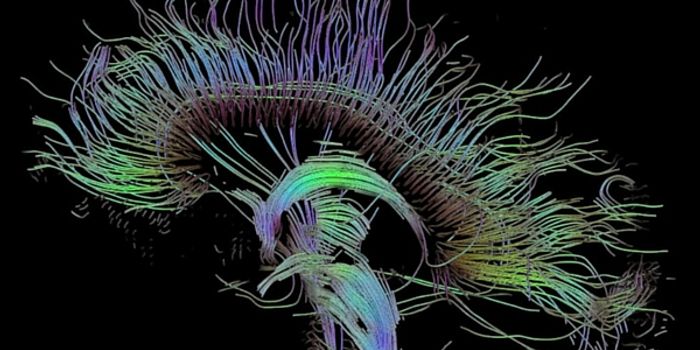

JUN 30, 2016NeuroscienceWhen there has been a traumatic brain injury (TBI) or there is a tumor or other problem in the brain, doctors need to kn ...

MAR 01, 2016NeuroscienceThe vast network of neurons, dendrites, axons and other hardware that is responsible for sending messages all over the b ...

JAN 29, 2016Clinical & Molecular DXPrecision medicine makes its way to one of the most complicated organs in the body: the brain. Researchers from the Univ ...

DEC 29, 2015NeuroscienceBrain injuries and neurodegenerative diseases are devastating to those who suffer them and incredibly complex for the do ...